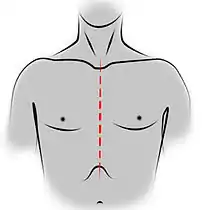

- Voies d'abord utilisées

Incision de sternotomie médiane pour une thymectomie trans-sternale.

Sur le plan technique, chaque voie d'abord présente des avantages et des inconvénients. La voie trans-sternale est réalisée par une sternotomie médiane, la cicatrice parcourant toute la hauteur du sternum. On s'expose ainsi au risque d'infection du sternum, et l'ensemble de la cavité pleurale n'est pas facilement accessible[82]. En revanche, il est facile d'étendre l'incision au cou, en cas d'une tumeur cervicothoracique, et de réaliser une exérèse devant emporter les organes adjacents : pneumonectomie ou lobectomie pulmonaire et geste sur les gros vaisseaux du médiastin ne sont possibles de manière optimale que par cette voie d'abord[82].